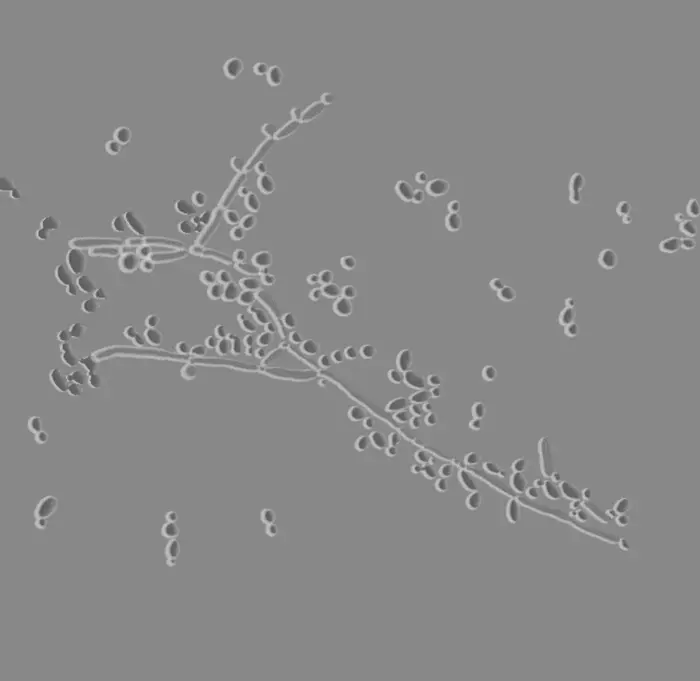

Levaduras ovales pequeñas, sólo gemación; test tubo germinal negativo. Identificación confirmada por PCR o sistemas automatizados. Se recomienda determinar MIC por su posible resistencia antifúngica (66).